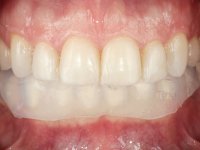

Paciente do sexo masculino, com 36 anos, não fumador. Fez tratamento ortodôntico e reabilitou esteticamente o sector anterior com restaurações em resina composta. As restaurações apresentavam um aumento vertical médio de 2 mm em relação o bordo incisal. Apresentavam-se esteticamente satisfatórias, mas com algumas fraturas incisais. O dente 1.5 apresentava um processo apical e o dente 2.6 apresentava tratamento endodôntico e uma lesão endo-periodontal. No maxilar inferior no local do dente 3.5 apresentava um implante com uma coroa aparafusada e o dente 8.5 ainda estava presente em boca com agenesia do dente 4.5. O paciente apresentava uma ligeira perda da dimensão vertical da oclusão provavelmente associada a um visível desgaste das superfícies oclusais. O periodonto era espesso e apresentava uma excelente higiene oral.

Após análise clínica e imagiológica foi proposto ao paciente recuperar a dimensão vertical da oclusão essencialmente à custa de incrementos oclusais inferiores utilizando “overlays” no sector posterior e facetas no sector anterior. A coroa aparafusada sobre o implante 3.5 seria substituída, no sentido de acompanhar este incremento. Na maxila o dente 2.6 teria extração indicada e posteriormente seria reabilitado com um implante e respetiva coroa. No sentido de reabilitar esteticamente o paciente duma forma minimamente invasiva, foi proposta a colocação de facetas feldespáticas no sector antero-superior. O objetivo de aumentar ligeiramente a D.V.O., teria como função “proteger” eficazmente o sector antero-superior.

Realizado o diagnóstico e tomada a decisão quanto ao tratamento a executar, tornou-se importante definir qual a sequência de trabalho a adotar no sentido de conseguir a reabilitação da D.V.O. (V.D.O), de forma progressiva e equilibrada. Na primeira fase fez-se uma pré-impressão da arcada inferior com silicone tipo “putty” e em seguida realizou-se o preparo dentário de todo o sector posterior. O preparo para os overlays foi feito coronalmente à linha amelo cementaria no sentido de ser o mais conservador possível. A impressão foi feita com técnica de dupla mistura após afastamento gengival realizado com pasta de caulino. A provisória foi realizada com resina composta de polimerização dual. Em laboratório foram realizados os overlays após se ter aberto ligeiramente (1,5mm) a D.V.O. nos modelos montados em articulador semi-ajustável. Simultaneamente o sector antero-inferior foi encerado no sentido de acompanhar este aumento da D.V.O. Também foi confecionada uma chave de silicone translucido para posterior confeção dos provisórios antero-inferiores. Em boca foi primeiro realizada a provisionalização dos dentes anteriores utilizando resina composta previamente aquecida após preparação das superfícies dentárias para a adesão. Foi colocado o dique de borracha para promover o isolamento absoluto e posteriormente foram colados os overlays. Em laboratório foi realizada nova chave de silicone para confecionar os provisórios antero-superiores. Seguidamente em boca foram preparados os seis dentes antero-superiores após colocação do fio de afastamento gengival. Feita a preparação adequada das superfícies dentárias foi realizada a impressão com técnica de dupla mistura e a respetiva provisória. Em laboratório foram confecionadas 6 facetas feldespáticas num modelo de trabalho tipo “Geller”. A provisória foi removida e as facetas foram coladas em boca utilizando um isolamento relativo competente. Esta opção foi tomada em virtude de uma prévia experiencia negativa com a colocação do dique de borracha na mandibula. Após a colagem dos laminados antero-superiores foram dadas 12 semanas para avaliar a adaptação do paciente à nova situação e então iniciar a confeção das facetas antero-inferiores. Após colocação do fio de afastamento gengival. foram feitos os preparos dentários adequados e em seguida foi feita a impressão. Também foi feita a preparação do dente 3.4 que, entretanto, tinha sofrido uma fratura do overlay. As facetas e a restauração do 3.4 foram realizadas num modelo de trabalho tipo “Geller”. Após remoção da provisória, as facetas foram coladas em boca, utilizando um isolamento relativo pelas razões apontadas anteriormente. Após colocação do trabalho o paciente foi reabilitado por outros colegas com um implante na zona do 2.6 e substituição da coroa aparafusada sobre o implante colocado no local do 3.5. Posteriormente surgiram fraturas nos overlays dos dentes 4.7 e 3.7 que foram reabilitados com overlays em Zr.